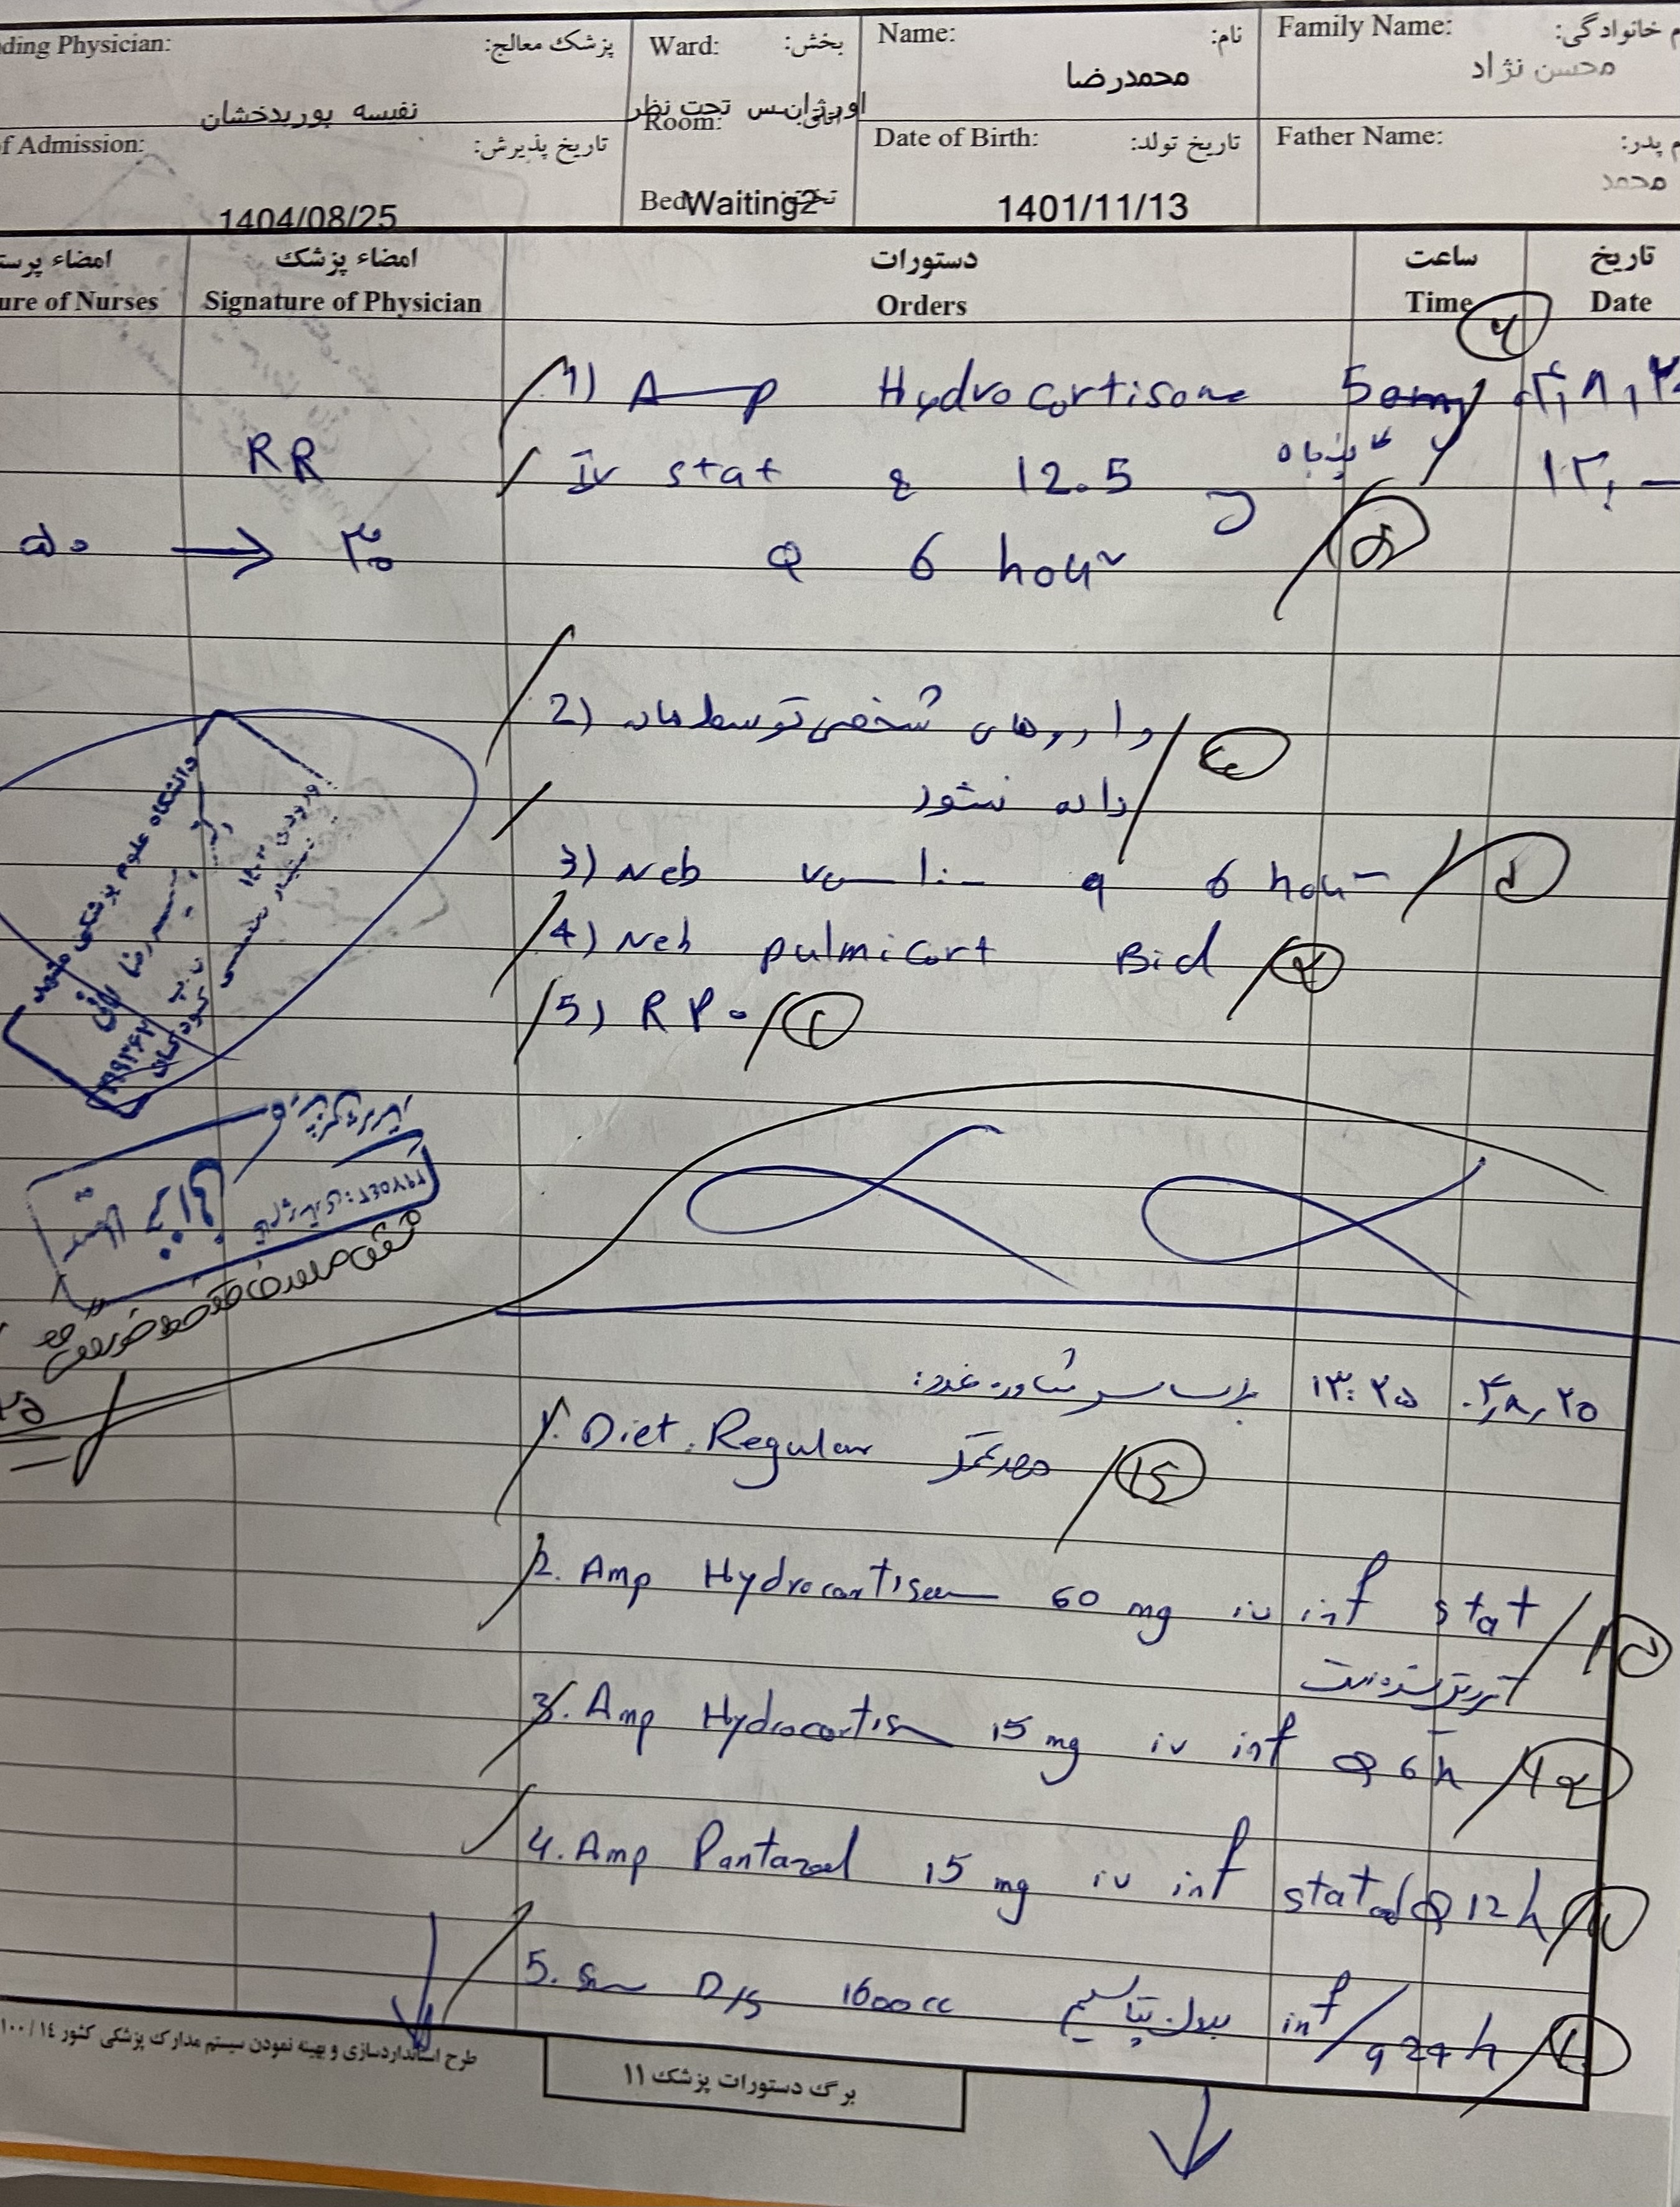

بیمار پسر ۲ سال ونه ماه مورد cah از ۱۷ روزگی تشخیص شده (با علایم اولیه poor feeding و تیرگی پنیس و لب وپتاسیم ۹ )با سرفه prوتب از دیشب شروع شده به اورژانس مراجعه کرده وهمچنین ۳ نوبت استفراغ داشته وابریزش بینی وسایقه بستری مکرر داشته با شک به گریز ادرنال بستری شدن

هیدروکورتیزون ۱۰ میلی

هر ۸ ساعت

فلودروکورتیزون هر ۸ ساعت / دوز دوبرابر شده بعد از بروز علایم

پسر 2ساله ونه ماه با تب وسرفه وابریزش و۳ بار استفراغ از دیشب به اورژانس مراجعه کرده مورد cah از ۱۷ روزگی تحت درمان با هیدروکورتیزون و فلودروکورتیزون بوده با شک به کریز ادرنال بستری شدن تاکی پنه وتاکی کاردی داشته